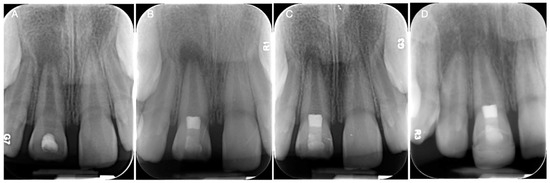

| Kim and Solomon, 2021 [66] | In vivo | Twenty-four roots from mature canine premolars were equally divided into three groups: blood clots (BC), collagen membranes (CM), and dHACMs.

| Fibrous connective tissue was present in all groups, most predominatly in the dHACM group. Odontoblast-like cells were found only in the dHACM group. Intracanal mineralized tissue was observed only in the BC and CM groups. More periapical inflammation was observed in the BC group than in the dHACM group. | dHACMs may be useful for cell homing-based pulp regeneration in mature teeth. |